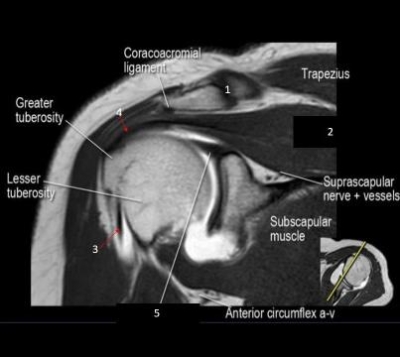

2. Observe esta imagem. Que estrutura corresponde ao número 5?

5. Observe a imagem acima. Que estrutura o número 5 se refere?

8. Observe esta imagem. Que estrutura corresponde ao número 2?